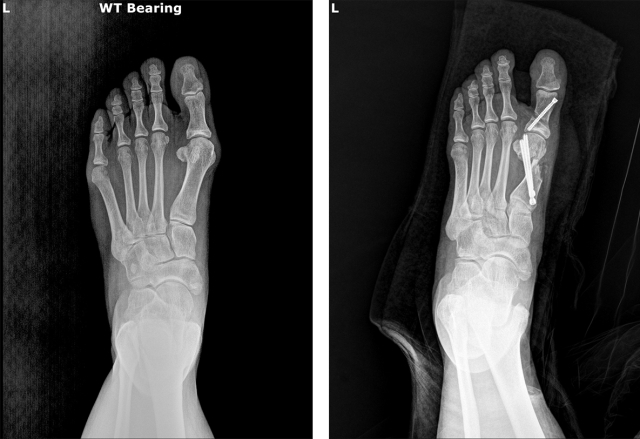

무지외반증의 치료법은 지속적인 연구와 학술 활동을 통해 발전해 왔는데, 최근 무지외반증에 적용되는 수술 방법으로는 절개 범위를 줄이고 회복을 빠르게 하는 최소침습 수술(MICA: Minimally Invasive Chevron-Akin Osteotomy)이 점차 널리 시행되고 있다.

약 1㎝ 미만의 작은 절개로 특수 기구를 넣어 뼈를 자르고 교정한 뒤, 실시간 투시 영상(C-arm)으로 교정 상태를 확인하며 나사로 고정한다. 보고된 장점으로는 출혈과 부종이 적고, 흉터가 거의 남지 않으며, 비교적 빠른 시기에 체중 부하와 일상생활 복귀가 가능하다는 점 등이다.